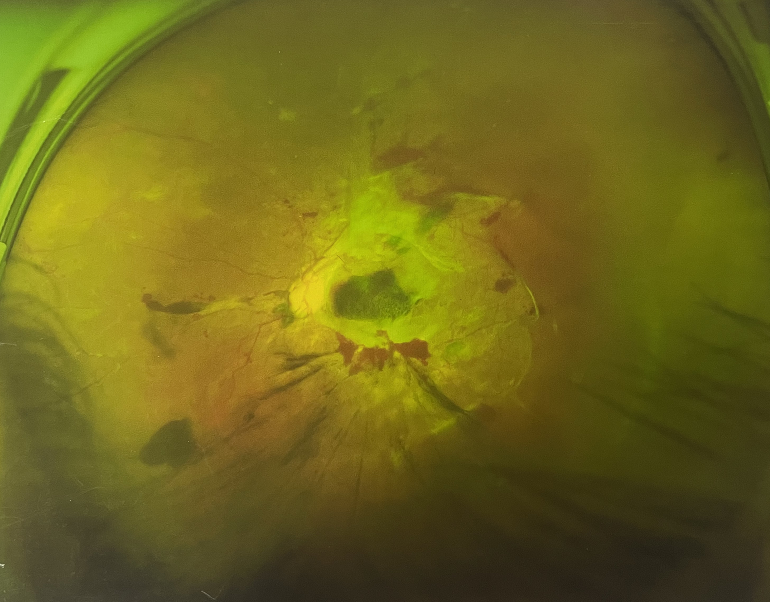

眼底出血一般多久能好?眼底出血可以由眼科本身疾病引起,常見的是視網(wǎng)膜靜脈阻塞、糖尿病視網(wǎng)膜病變、中心性滲出性視網(wǎng)膜病變、視網(wǎng)膜動脈硬化、老年性黃斑病變、視網(wǎng)膜靜脈周圍炎。

另外,眼底出血還可以由全身疾病引起,比如糖尿病可以引起眼底出血,高血壓也會引起眼底出血,還有嚴重的腎病,血液方面的疾病都可以導致眼底出血。

眼底出血一般多久能好?眼底出血如果是輕癥,時間較短的患者大約3-6個月可以恢復,如果是重癥或者病程較長的患者,可能要持續(xù)1年,甚至2年時間。

眼底出血一般多久能好?眼底出血是醫(yī)生用檢眼鏡才能看到,患者和其他人看不見。眼底出血不是單獨的病,一般來說是由眼科本身疾病造成,還可以由全身疾病造成。比如常見的視網(wǎng)膜靜脈阻塞、糖尿病視網(wǎng)膜病變等引起的眼底出血較常見。眼底出血一般多久能好?所以眼底出血的出血吸收時間也不一樣,要根據(jù)病情輕重決定其預后,出血吸收時間也不一樣。